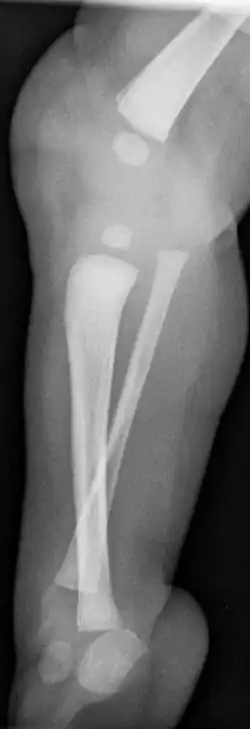

• Typ III Dysplasie der Tibia distal mit tibiofibulärer Diastase (Fehlanlage der Sprunggelenksgabel)

Bereits im Mutterleib kann während einer Ultraschalluntersuchung die Fehlbildung erkannt werden,[2] die Verkürzung und Fehlstellung des Unterschenkels ist nach der Geburt offensichtlich. Ein Röntgenbild kann das Ausmaß der Fehlbildung sowie zusätzliche knöcherne Veränderungen dokumentieren. Mittels Sonographie können die knorpeligen Anlagen und deren Stellung zum Gelenk sicher dargestellt werden, wesentlich bei den Typen II und III.

• Typ III: Hier muss operativ ein funktionelles Sprunggelenk erzeugt werden[10]